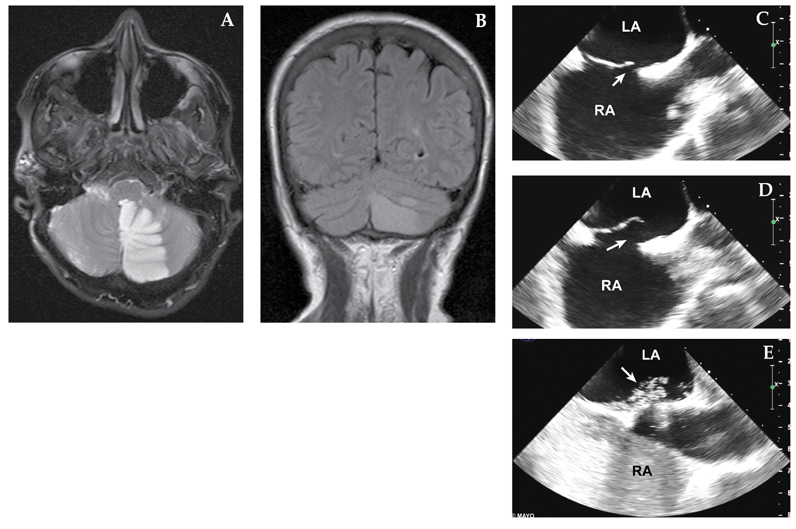

A 63-year-old woman who had a remote history of migraine awakened with a headache with visual aura, as well as nausea, vomiting and incoordination. She was a former smoker but had no history of hypertension, estrogen replacement or family history of stroke. A and B. MRI demonstrated a left cerebellar infarct. C and D. Transesophageal echocardiography demonstrated a large PFO (arrow) with an atrial septal aneurysm. E. Contrast injection demonstrated generous flow across the PFO (arrow) with Valsalva. Percutaneous closure was performed. LA, left atrium; RA, right atrium.

The prevalence of PFO in the adult general population may be as high as 25 percent; usually these interatrial shunts are asymptomatic and of no hemodynamic importance. Until the advent of echocardiography, it was difficult to diagnose PFO antemortem. Transthoracic imaging, especially with agitated saline contrast injection, transesophageal echocardiography and transcranial Doppler, is widely used to identify and characterize PFO.